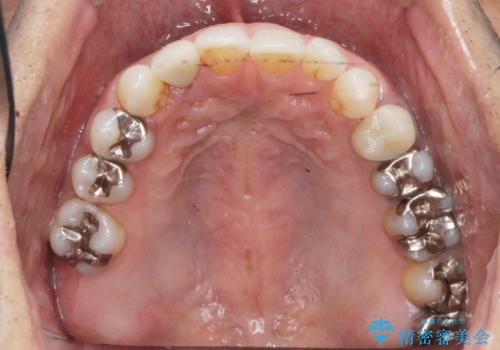

[ セラミック治療 ]目立つ奥歯の銀歯を白くする

![[ セラミック治療 ]目立つ奥歯の銀歯を白くするの症例 治療前](https://seimitsushinbi.jp/wp/wp-content/uploads/2021/11/200905b82e48a56c05450d91be582e11-1-500x350.jpg?v=1637229926)